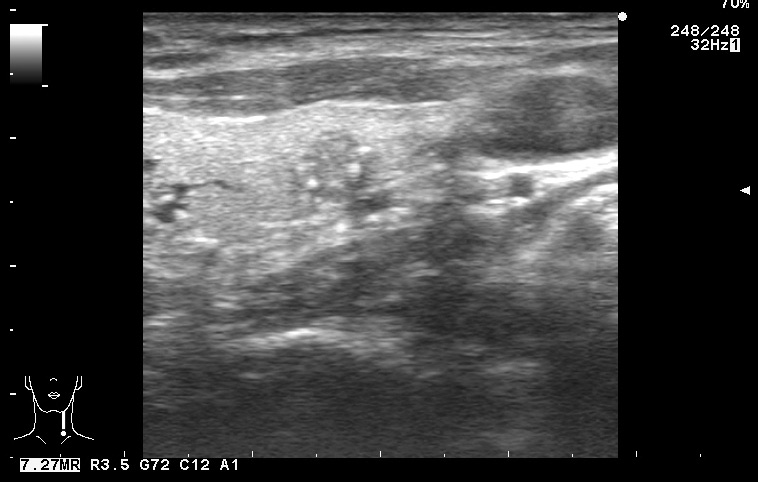

Папиллярная карцинома, УЗИ

Мужчина средних лет.

изоэхогенный узел с кальцинатами

Типичная картина, кстати.

Папилляная карцинома.

Диагноз доказан морфологически (ТАБ, гистология).